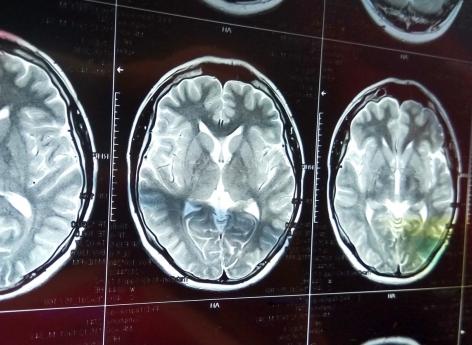

Première cause de mortalité chez la femme et première cause de handicap physique acquis de l’adulte, l’accident vasculaire cérébral (AVC) touche chaque année 140 000 patients. Survenant en moyenne à l’âge de 74 ans, l’AVC correspond à une perte soudaine de la fonction d’une partie du cerveau, provoquée soit par un arrêt brutal de la circulation sanguine à l’intérieur d’une artère du cerveau, soit par la rupture d’une artère avec saignement dans le crâne ou le cerveau.

Représentant 80% des AVC, les infarctus cérébraux sont principalement la conséquence de l’obstruction d’une artère cérébrale par un caillot sanguin. Dans la majorité des cas, cette obstruction est due à l’athérosclérose, c’est-à-dire la formation d’une plaque d’athérome dans une artère qui, en s’ulcérant, amènera à la formation d’un caillot sanguin. C’est la migration de ce caillot ou d’un morceau de la plaque athérome qui bouchera l’artère cérébral et provoquera l’AVC.

L’hémorragie cérébrale ou méningée : la rupture d’une artère

Représentant respectivement 15% et 5% des AVC, les hémorragies cérébrales et méningées correspondent à la rupture d’une artère au niveau du cortex ou des méninges qui l’entourent. Ces AVC sont considérés comme les cas les plus graves. Cette rupture concerne le plus souvent une artère de petit calibre, fragilisée par l’hypertension artérielle chez les personnes âgées. La rupture d’une malformation vasculaire cérébrale préexistante (anévrysme ou malformation artério-veineuse) ou un trouble de la coagulation (souvent lié à la prise de médicaments anticoagulants) peuvent également être à l’origine d’une hémorragie cérébrale, souvent chez des personnes plus jeunes.